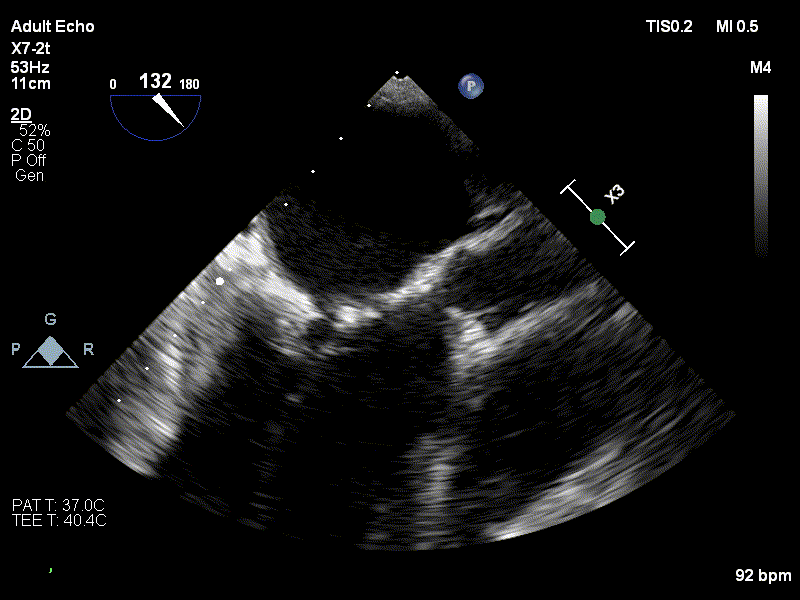

Diagnosticul de stenoză mitrală strânsă degenerativă a fost stabilit pe baza examenului ecocardiografic, realizat de dr. Irina Macovei-Dorobanțu, medicul cardiolog care s-a ocupat de pacienta pe toată durata spitalizării.

1. Imagine ecografie transesofagiană valva mitrală cu calcificări importante la nivelul cuspelor și al inelului, cu mobilitate limitată a cuspelor

2. Imagine ecografie transesofagiană, valvă mitrală cu regurgitare minimă și stenoză semnificativă